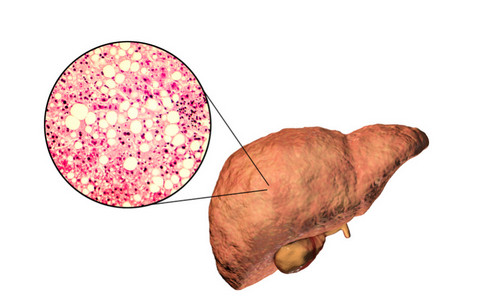

지방간은 간세포에 지방이 무리하게 축적되면 발생하는 질병입니다. 이러한 지방간은 최근들어 그 발병률이 올라가 주변에서 흔히 관찰되는 질병 중 하나가 되었습니다. 지방간은 절대 경시해서는 안 되며, 방치 시 심각한 합병증이나 간암으로 진행될 수 있습니다. 약 4명 중 1명이 지방간에서 간경변증으로 진행되는데, 이럼에도 불구하고 많은 사람들이 지방간을 대수롭지 않게 여기는 경향이 많습니다.

지방간은 만성 염증 증상으로 간 조직이 섬유화되어 간 기능이 손상됩니다. 이에 따라 복수, 간성뇌증, 황달, 정맥류 출혈과 같은 합병증이 발생할 수 있습니다. 음주가 지방간과 많은 연관이 있는데, 남성은 일주일에 3~4병, 여성은 2병 정도의 주량으로 소주를 마시면 지방간 발생 가능성이 높아진다고 합니다.

지방간의 원인 중 하나로 과식이 알려져 있습니다. 특히 사무실에서 일해 활동이 부족한 사람들은 특별히 주의해야 합니다. 과도한 칼로리는 중성 지방과 글리코겐으로 몸에 축적될 수 있습니다. 이러한 지방이 내장과 피부 지방으로 축적되며, 간에도 저장되면서 간세포에서 중성 지방이 30% 이상 축적되면 '지방간'으로 진단됩니다.

비만이 아니더라도, 내장 지방과 간 내의 지방 축적은 구별되기 때문에 어떤 경우에는 겉으로 마른 사람도 지방간으로 진단될 수 있습니다. 지방간은 초기 단계에서는 자각하기 어렵고, 피로나 경미한 불쾌감과 같은 증상만 나타날 수 있습니다. 그러나 병이 진행되면 간염이나 간경화로 이어질 수도 있습니다.